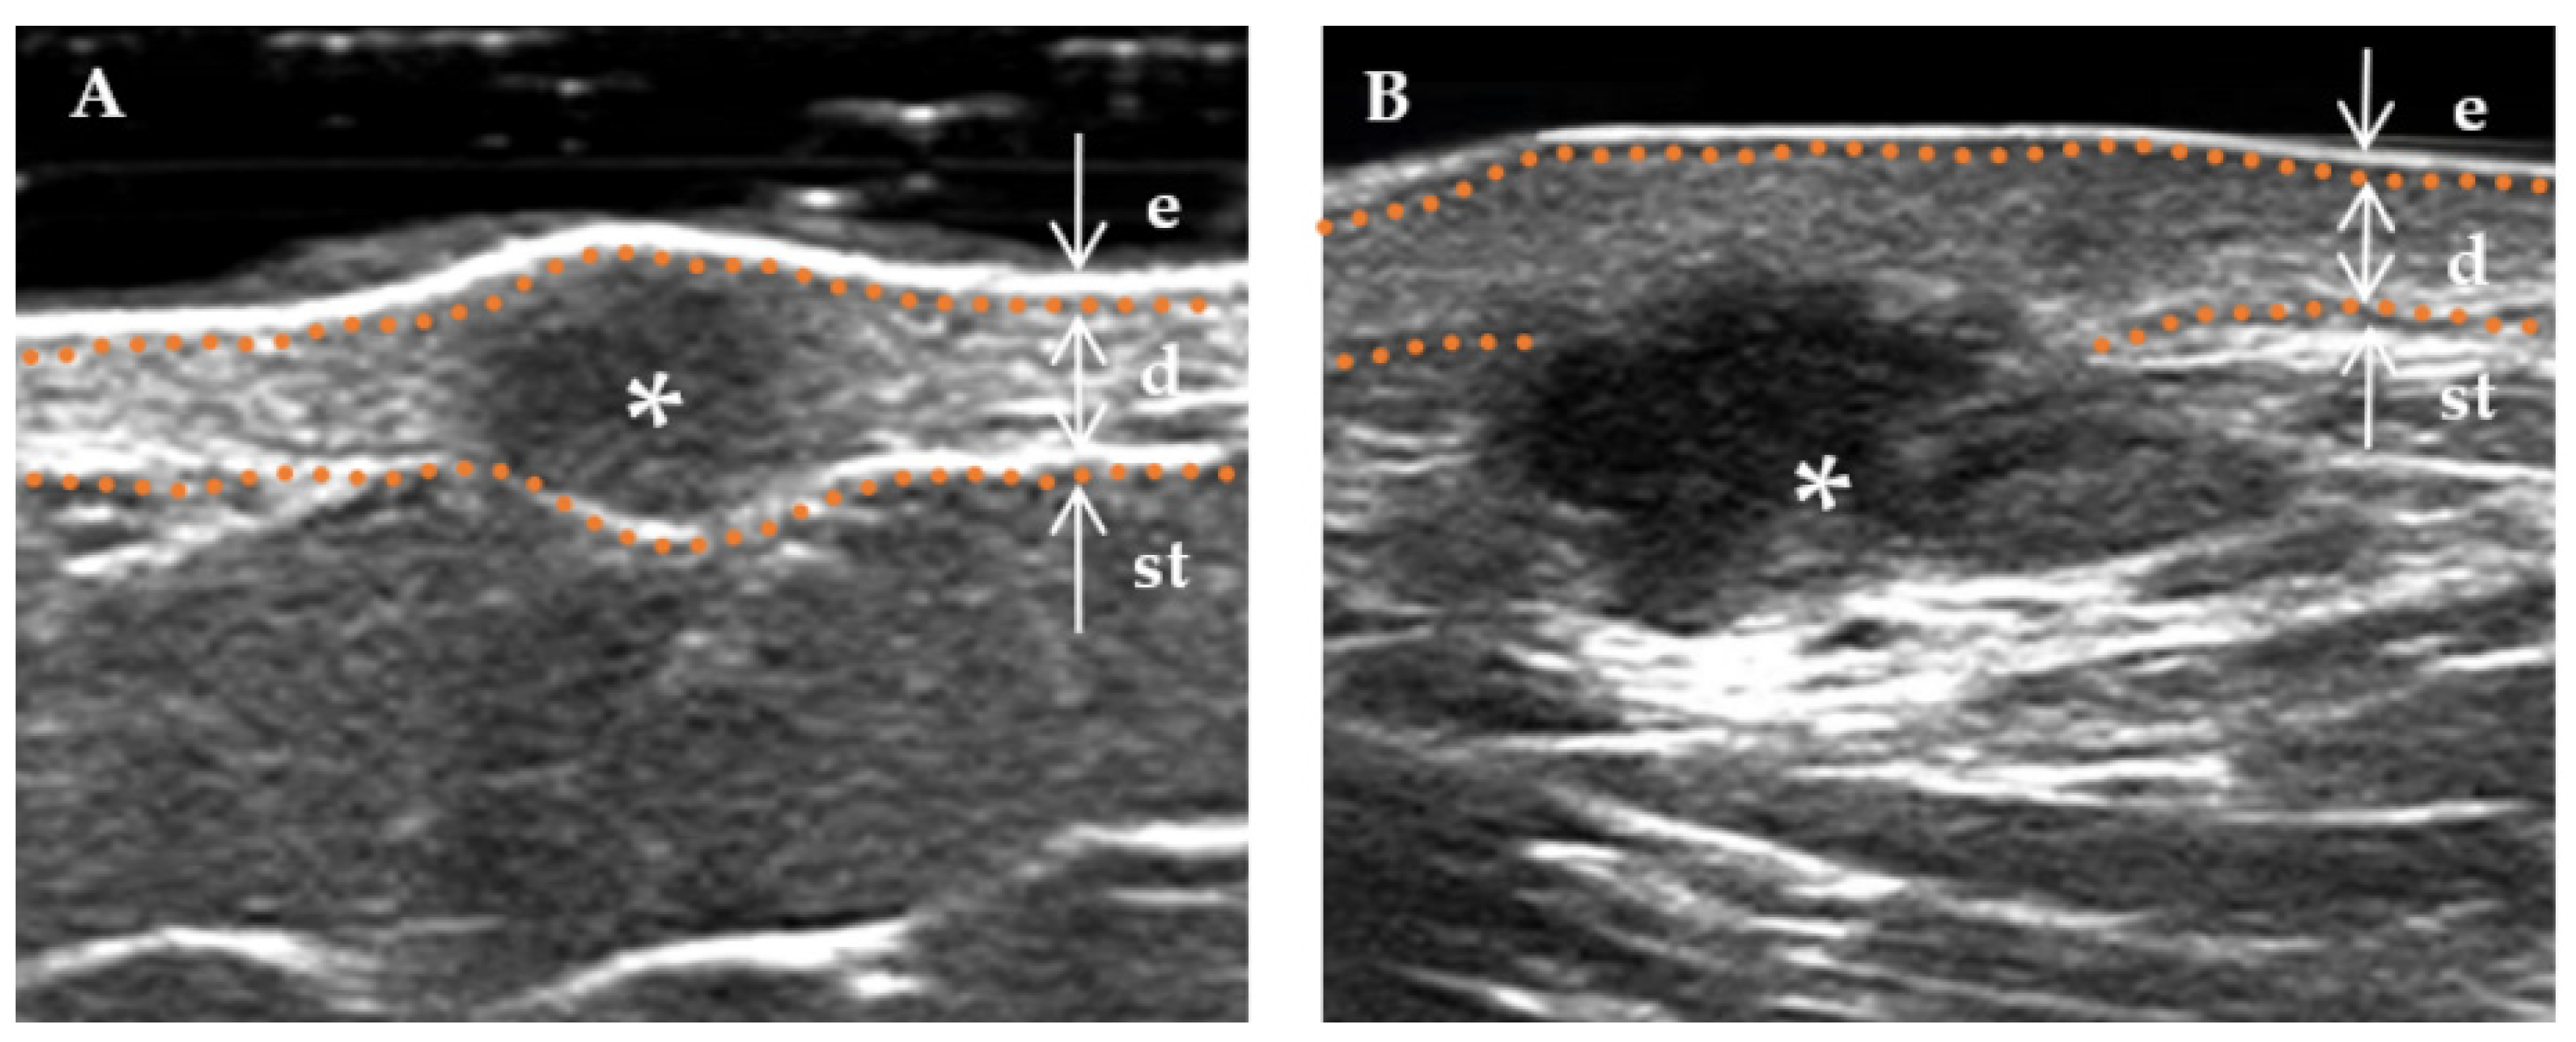

Figure 2.

Boundary of a DF lesion. * Indicates the precise location of the lesion on the ultrasound image. The skin layers are indicated by dotted orange lines, with arrows indicating a hyperechoic epidermis (e), an isoechoic dermis (d), and a subcutaneous tissue (st). The boundary of the lesion (indicated by a white triangle) is distinctly demarcated. (A) “Regular” lesions are characterized by smooth edges without infiltration into the adjacent tissue. (B) “Irregular” lesions are characterized by jagged edges that can penetrate the surrounding dermis or subcutaneous tissue.